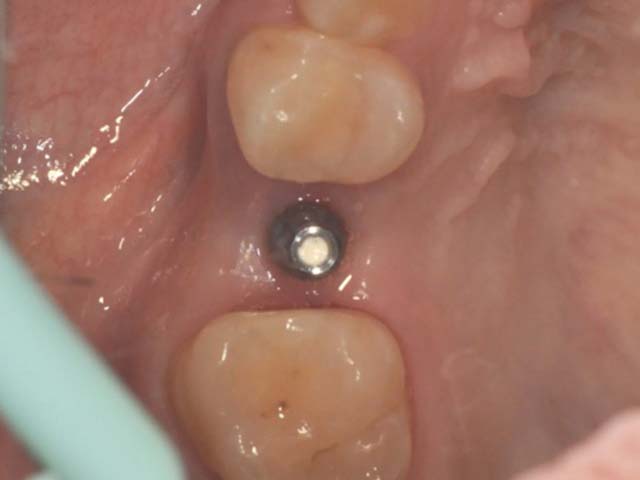

齒槽骨保存術+植牙 首頁 案例分享 人工植牙 齒槽骨保存術+植牙 STEP1拔除掉無法使用的斷裂牙根 STEP2齒槽骨保存術—使用骨粉填補拔牙傷口 術前 V.S 術後 植牙第一階段—植入牙根 植牙第二階段—製作正式假牙